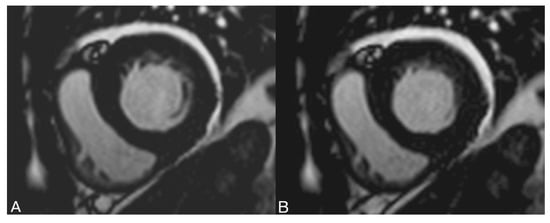

2.2.1. MR Parameters

2.2.2. Volume Determination with the Pixel-Based Method (PbM)